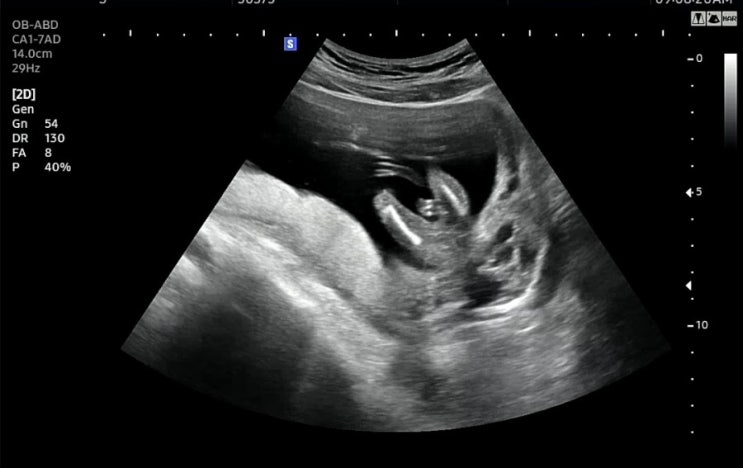

임신23주차/정밀초음파, 경부길이, 양수량, 체중증가

#정밀초음파 #임신23주증상 #임신23주 #임신체중증가 #경부길이 #AFI 임신 23주차 정밀초음파를 하러갔...